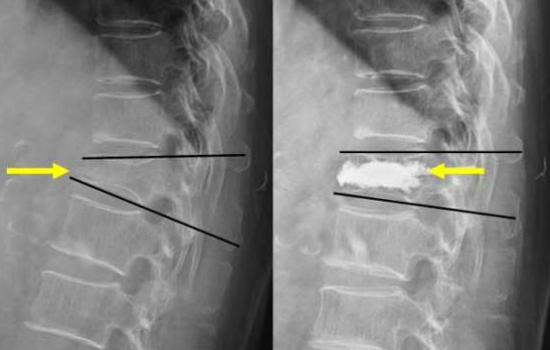

척추뼈의 골절이 발생한 부위에 골시멘트를 이용해 간단하게 시술 합니다. 부러진 척추뼈 속으로 유동체 골시멘트를 서서히 주입시키고 주입된 뼈 시멘트는 수 분 이내 딱딱하게 굳게 되며 부러진 척추뼈를 지지하게 됩니다.